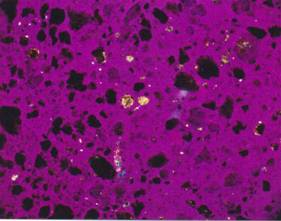

Pseudoizotropní agregáty apatitu se

stopami Whewellitu.

Zrnkový preparát, polarizační mikroskop, zvětšeno 160x